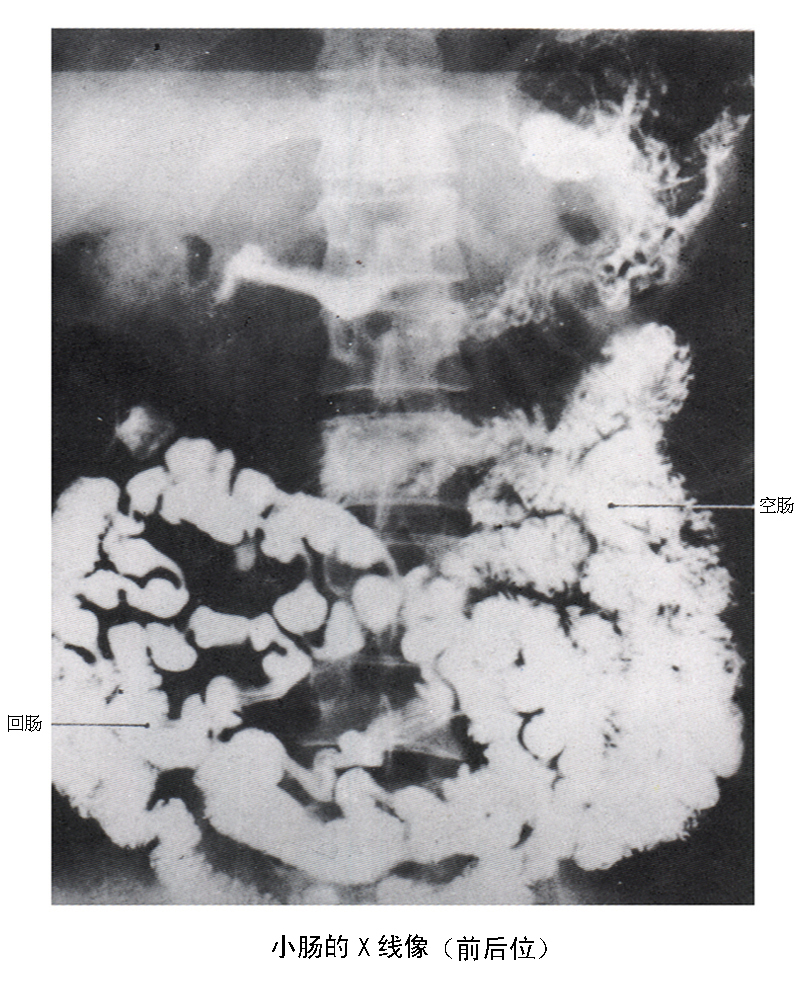

小肠的x线像(前后位)